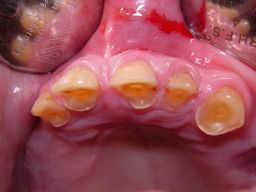

Die Bilder können alle angeklickt werden! Das Hauptproblem dieses Falles lag im Oberkiefer - die über die Jahrzehnte abgeknirschten, kurzen Zähne erschweren Kronen, die durch eine Prothese belastet werden können. Die gewählte Lösung besteht darin, die Zähne nur rundherum zu beschleifen, aber nicht mehr zu kürzen und die Prothese mit einem Druckknopfsystem an die Zähne anzukoppeln, das ein "Spiel" aufweist, so daß die Prothese nicht als Hebelarm auf die schwachen Restzähne wirken kann. Rechts die beschliffenen Zähne kurz vorm Zementieren der Kronen. |